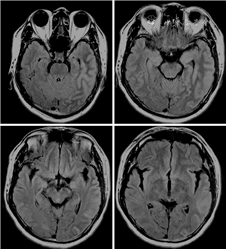

本次入院体检:体温36.6 ℃,脉搏83次/min,呼吸18次/min,血压140/93 mmHg(1 mmHg=0.133 kPa),心肺腹未见异常,意识清楚,言语流利,精神可,脑神经正常,高级神经活动正常,四肢肌力Ⅴ级,肌张力正常,两侧肢体触觉、痛觉、位置觉无减退,指鼻试验、跟膝胫试验稳准,四肢腱反射(++),左侧Babinski征可疑阳性,右侧Babinski征未引出,颈抵抗,颏下约2横指,Kernig征、Brudzinski征阴性。辅助检查:尿便常规、血糖、电解质、凝血功能、心肌标志物、甲状腺功能、免疫全项、肿瘤系列、红细胞沉降率均正常,输血四项(乙肝表面抗原、丙型肝炎抗体、梅毒螺旋抗体、人类获得性免疫缺陷病毒)均阴性,直接胆红素4.1 μmol/L(正常值0~3.4 μmol/L),谷氨酰转移酶106 U/L(正常值0~60 U/L),尿酸451 μmol/L(正常值208~428 μmol/L),血白细胞计数12.81×109/L[正常值(4~10)×109/L],中性粒细胞绝对值9.2×109/L[正常值(2~7.5)×109/L],C反应蛋白13.4 mg/L(正常值0~8.0 mg/L)。风湿抗体:抗链“O”试验697 IU/ml(正常值0~200 IU/ml),余项均正常,抗中性粒细胞胞质抗体阴性。脑脊液结核分枝杆菌DNA、RNA检测均阴性。脑脊液结核抗体、隐球菌抗原检测均阴性。脑脊液结核分枝杆菌培养、真菌培养、普通菌培养均阴性。脑脊液革兰染色、墨汁染色、结核菌涂片均阴性。脑脊液猪囊虫抗体、布鲁杆菌抗体均阴性。送检天津市儿童医院结果示:脑脊液风疹病毒IgM、柯萨奇病毒IgM+IgG、巨细胞病毒IgM、EB病毒抗体、单纯疱疹病毒1型抗体、单纯疱疹病毒2型抗体均阴性;风疹病毒、巨细胞病毒、单纯疱疹病毒、肺炎支原体、结核杆菌DNA均阴性。送检北京协和医院结果示:血和脑脊液自身免疫性脑炎抗体(抗N-甲基-D-天冬氨酸受体抗体、抗接触蛋白相关蛋白2抗体、α氨基-3-羟基-5-甲基-4-异噁唑丙酸1型受体抗体、α氨基-3-羟基-5-甲基-4-异噁唑丙酸2型受体抗体、富亮氨酸胶质瘤失活1蛋白抗体、γ-氨基丁酸B型受体抗体、抗谷氨酸脱羧酶65抗体)均阴性。送检北京海思特医学检验实验室结果示:脑脊液抗水通道蛋白4抗体IgG阴性,血和脑脊液抗胶质纤维酸性蛋白抗体IgG阴性,血抗髓鞘少突胶质细胞糖蛋白抗体IgG阴性。头颅MRI示左侧颞枕顶叶脑回略肿胀,左枕顶叶脑回及部分脑沟炎性改变(图1)。头颅MRV增强扫描未见明显异常。